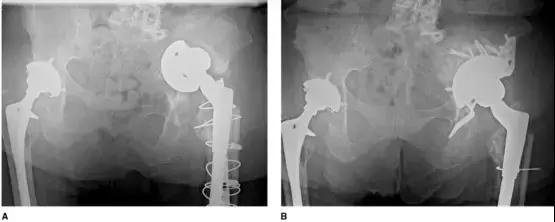

近年来出现了一种新的 cages 与 Jumbo 杯的组合(cup-cage 技术),Jumbo 杯充当垫块的角色,适用于骨盆不连续、骨质量较差的病例,但该技术尚缺乏长期的随访数据(图 6、7)。

图 6(A)尸体解剖显示骨盆不连续(B)半球形的 Jumpo 杯压配植入,并用螺钉固定,外展角更大,前倾角更小,以适应 cage 的坐骨翼。用尖骨刀在坐骨上凿出一个凹槽(C)cage 通过凹槽嵌进坐骨,并用螺钉固定在髂骨上(D)聚乙烯内衬用骨水泥固定,更小的外展角,更大的前倾角以适应 cage 的位置

图 7 (A)术前骨盆平片显示左髋严重髋臼骨缺损和髋臼假体垂直脱位(B)cup-cage 技术翻修术后骨盆平片